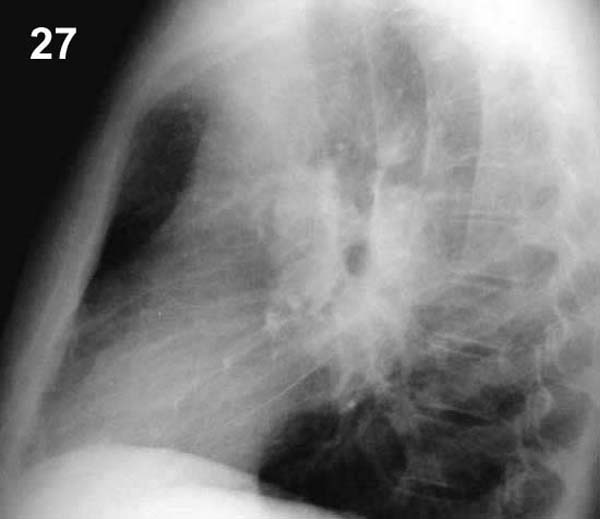

Placa 27

Las masas rodean las sombras aéreas redondeadas correspondientes a los bronquios principales, confirmando la situación hiliar. Si las masas estuvieran por delante o por detrás del corazón en la placa frontal también aparecerían proyectadas sobre los hilios. En este caso la etiología más probable es una sarcoidosis, pero esto no puede afirmarse mientras otros datos clínicos y exámenes no lo confirmen.